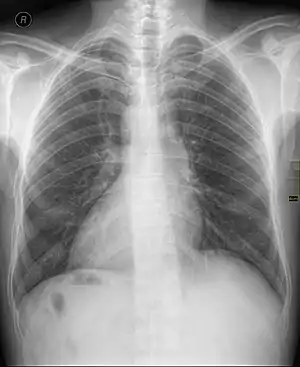

Dextrocardia

Dextrocardia é uma anomalia congênita relativamente rara em que o coração está virado para o lado direito do corpo. Pode ocorrer de forma isolada (Situs Inversus solitus) ou junto com outros órgãos (Situs Inversus totalis). Estão associados com um risco aumentado de diversas doenças, mas cerca de 90% dos casos não apresentam sintomas perceptíveis.[1]